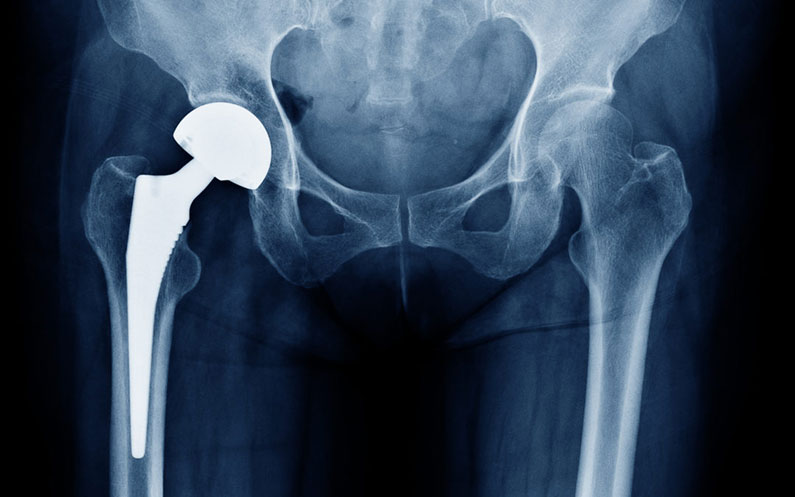

L’intervento consiste nella sostituzione di una o entrambe le componenti dell’articolazione dell’anca usurate. Infatti, l’articolazione si compone dell’acetabolo e la testa femorale. Quando si rende necessario sostituire entrambe le parti, si parla di protesi all’anca totale o Artroprotesi.

Quando la sostituzione riguarda solo la testa femorale o solo la parte acetabolare, parleremo invece di Endoprotesi.

Ancora, l’inserimento della protesi nell’osso può avvenire ad incastro o utilizzando un collante, per questo può essere definita protesi cementata o non cementata.